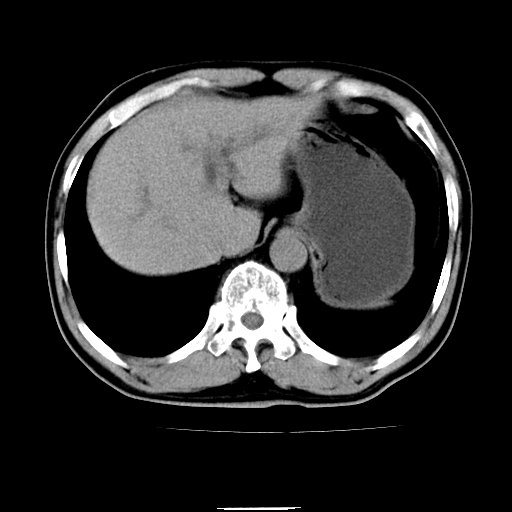

以下是引用chenqiong在2010-3-25 20:56:00的发言:[br]1、胆囊炎,胆囊息肉[br]2、肝内胆管及胆总管扩张,胆总管下端结石[br]3、十二指肠乳头旁憩室

以下是引用zxl51642在2010-3-26 10:47:00的发言:[br]胆囊炎,胆囊息肉,胆总管扩张,但未看到明显肿块,肝内胆管扩张不像恶性,炎性狭窄或阴性结石可能吧,建议mrcp,右肾小囊肿